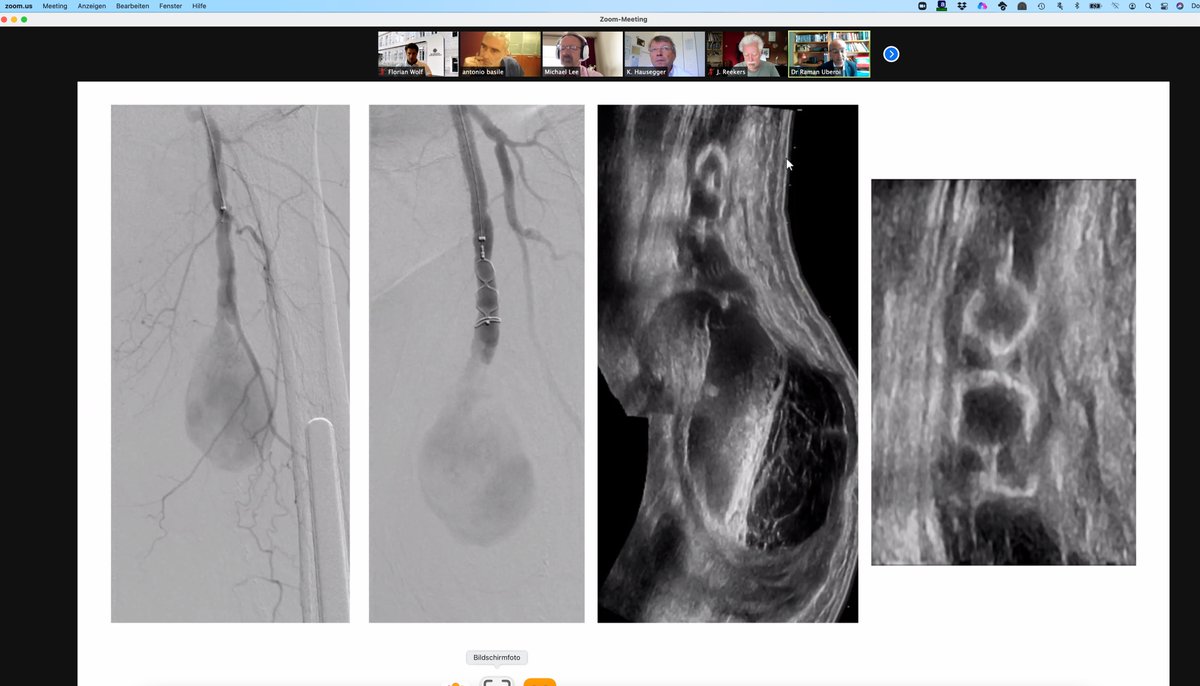

#CIRSEtakeover The beauty of prostate artery embolization in benign prostate hyperplasia patients - always a pleasure to see the blush of the prostate lobe before particle application. #PAE #BPH #ET2021 #CIRSE2021